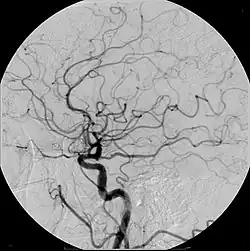

Современные контрастные препараты для внутривенного введения обычно содержат йод. Различают ионные и неионные контрастные препараты. Изначально были разработаны ионные йодсодержащие контрастные препараты, которые в настоящее время всё ещё используются в рентгенодиагностике. В неионных контрастных препаратах йод связан ковалентными связями, что заметно снижает риск осложнений. Имеет значение осмолярность контрастного препарата и концентрация в нём йода.